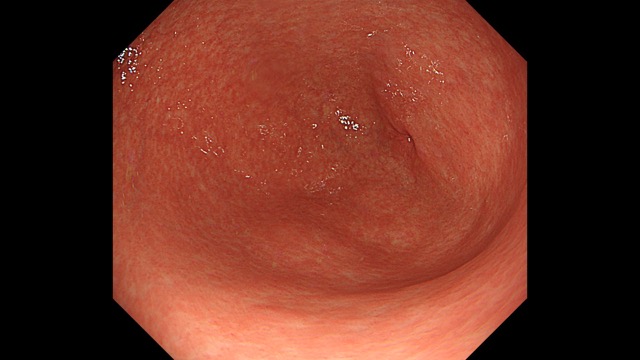

胃004